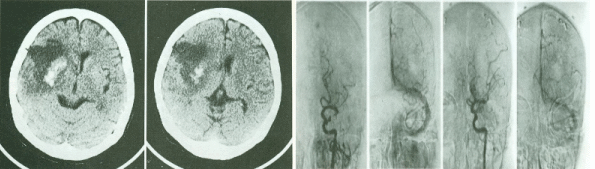

뇌지주막하출혈은 큰혈관이 어떤 원인에 의해 풍선꽈리처럼 부풀어 순간적으로 터지기 때문에 매우 위험할 수 있습니다. 33%는 출혈당시 사망하고 33%는 병원에 혼수상태로 내원하며, 30%정도가 심한 두통을 호소하여 병원으로 오게됩니다. 이때 두통은 매우 특징적이어서 마치 "망치로 뒷통수를 맞은것 같은 또는 머릿속에서 번개가 친다"라는 표현을 합니다.

일단 뇌컴퓨터 단층촬영(CT)을 시행 후 뇌지주막하 소견이 보이면 뇌혈관촬영을 시행해야합니다. 뇌혈관 촬영상 출혈된 부위를 확인한 후 일단 의료코일이나 겔을 이용해 터진부위를 막아보고 여의치 않으면 수술을 통해 풍선꽈리를 클립을 이용해 막아주어야 합니다. 이때 수술을 하지 않으면 거의 재출혈로 사망하게 됩니다.

본병원에서는 중재적 영상의학과 선생님과 신경외과 선생님이 협진을 통해 뇌지주막하 출혈 환자에 대해 최선을 다하고 있습니다.